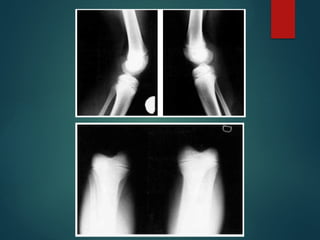

Rx

 En las rx laterales =

desplazamiento parcial

(subluxación) o luxación

completa de la tibia sobre el

fémur

 En las rx AP = subluxación lateral

o rotatoria asociada con

deformidad en valgo

 Hipoplasia o ausencia de los

centros de osificación

 TAC y RMN en casos severos y

planificación preoperatoria